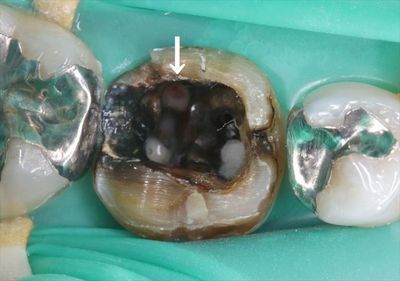

IMG_3620_R25.JPG

綿を取り除いた状態です。

矢印部分に穴が開いており、赤く軟組織が見えています。

白く膿も溜まっています。

根管治療時に根管の位置の見定めを誤って開けた穴と考えられます。

その証拠に、近心寄りの同じ位置にも今にも穴が開きそうなポイントが存在しています。

こちらは踏みとどまったようです。